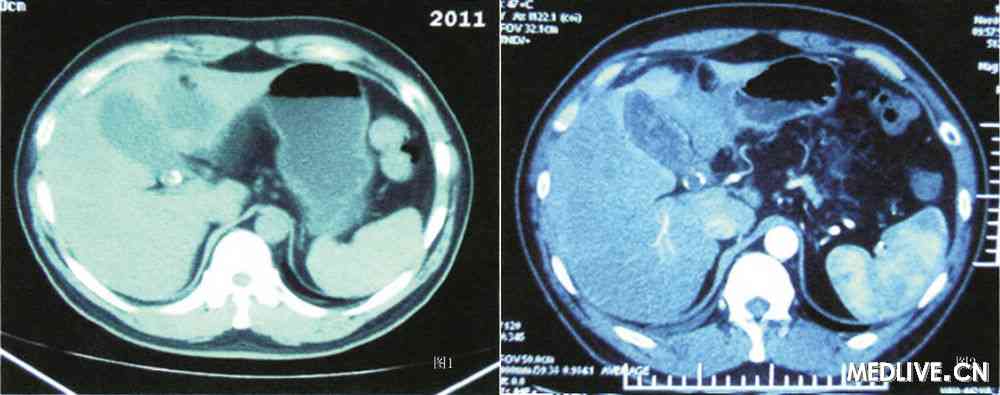

上腹部CT平扫(图1)示:肝脏表面光整,肝脏实质密度减低,胆囊颈部可见点状高密度区,胆囊实质内密度不均匀:进一步行增强CT(图2)示:胆囊壁明显强化,胆囊窝前内侧可见软组织样密度影; 影像诊断:胆囊结石,脂肪肝,胆囊窝积液。

(图1 入院上腹部CT平扫 图2上腹部CT增强)